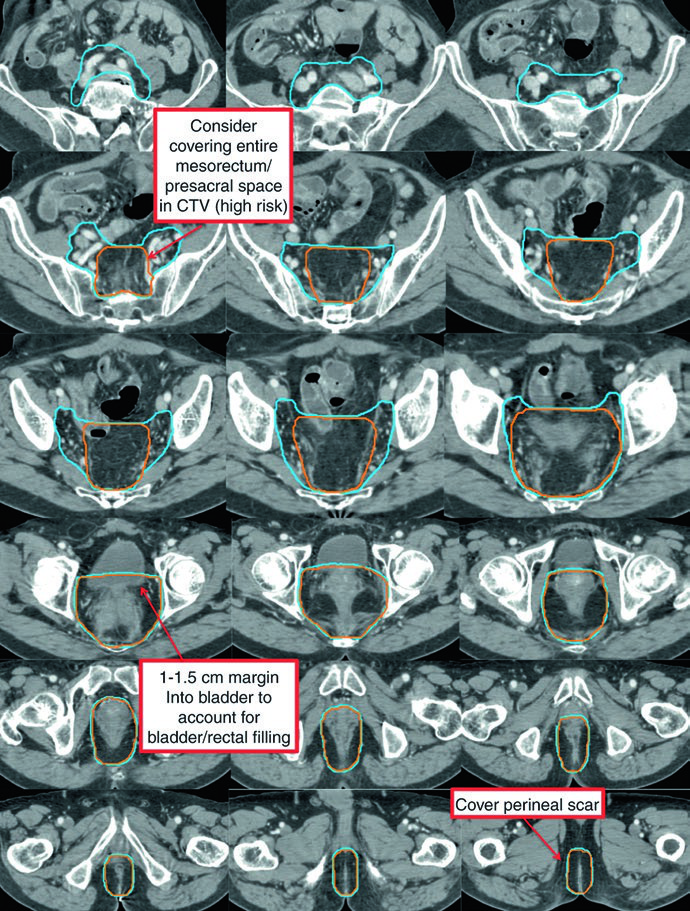

The high-risk CTV (CTV-HR) should include the GTV with a minimum 1.5 to 2 cm superior and inferior margin, plus the entire rectum, mesorectum, and presacral space. For grossly involved external iliac or inguinal nodes, the GTV-to-CTV margin should be at least 10 to 15 mm. In T4 tumors, a 1 to 2 cm margin into adjacent invaded organs (bladder, prostate, cervix) is added.

The standard-risk CTV (CTV-SR) covers the entire CTV-HR, mesorectum, and bilateral internal iliac lymph nodes. For T4 tumors with anterior organ involvement (bladder, cervix, prostate), the bilateral external iliac and obturator nodes must be included. If the primary tumor extends into the anal canal, bilateral external iliac and inguinal nodes are added to CTV-SR.

| CTV-HR | GTV-P and GTV-N with 1.5-2 cm margin superiorly and inferiorly, excluding uninvolved bone, muscle, and air. Minimum 10-15 mm margin for grossly involved external iliac or inguinal nodes. Entire rectum, mesorectum, and presacral space in the axial plane. 1-2 cm margin into adjacent organs for T4 tumors |

| CTV-SR | CTV-HR + entire mesorectum + bilateral internal iliac nodes. External iliac and obturator nodes for T4 with anterior organ involvement. Inguinal nodes for anal canal extension. Superior: L5/S1 or 2 cm above gross disease. Inferior: pelvic floor or 2 cm below gross disease. 0.7 cm margin around internal iliac vessels. 1-1.5 cm anterior margin into bladder |

T4 disease with anterior organ invasion significantly expands the treatment volume. The CTV-SR must cover the external iliac nodal region, and the anterior border of lateral fields needs adjustment to at least 1 cm anterior to the pubic symphysis.

In the postoperative setting, delineation follows similar principles to preoperative planning. After abdominoperineal resection (APR), the entire surgical bed — including the perineal scar — must be included. For macroscopic residual disease or positive margins, the CTV-P receives a 1 to 2 cm margin excluding uninvolved bone, muscle, and air. The postoperative CTV-HR covers the remaining rectum (if applicable), the mesorectal bed, and presacral space.